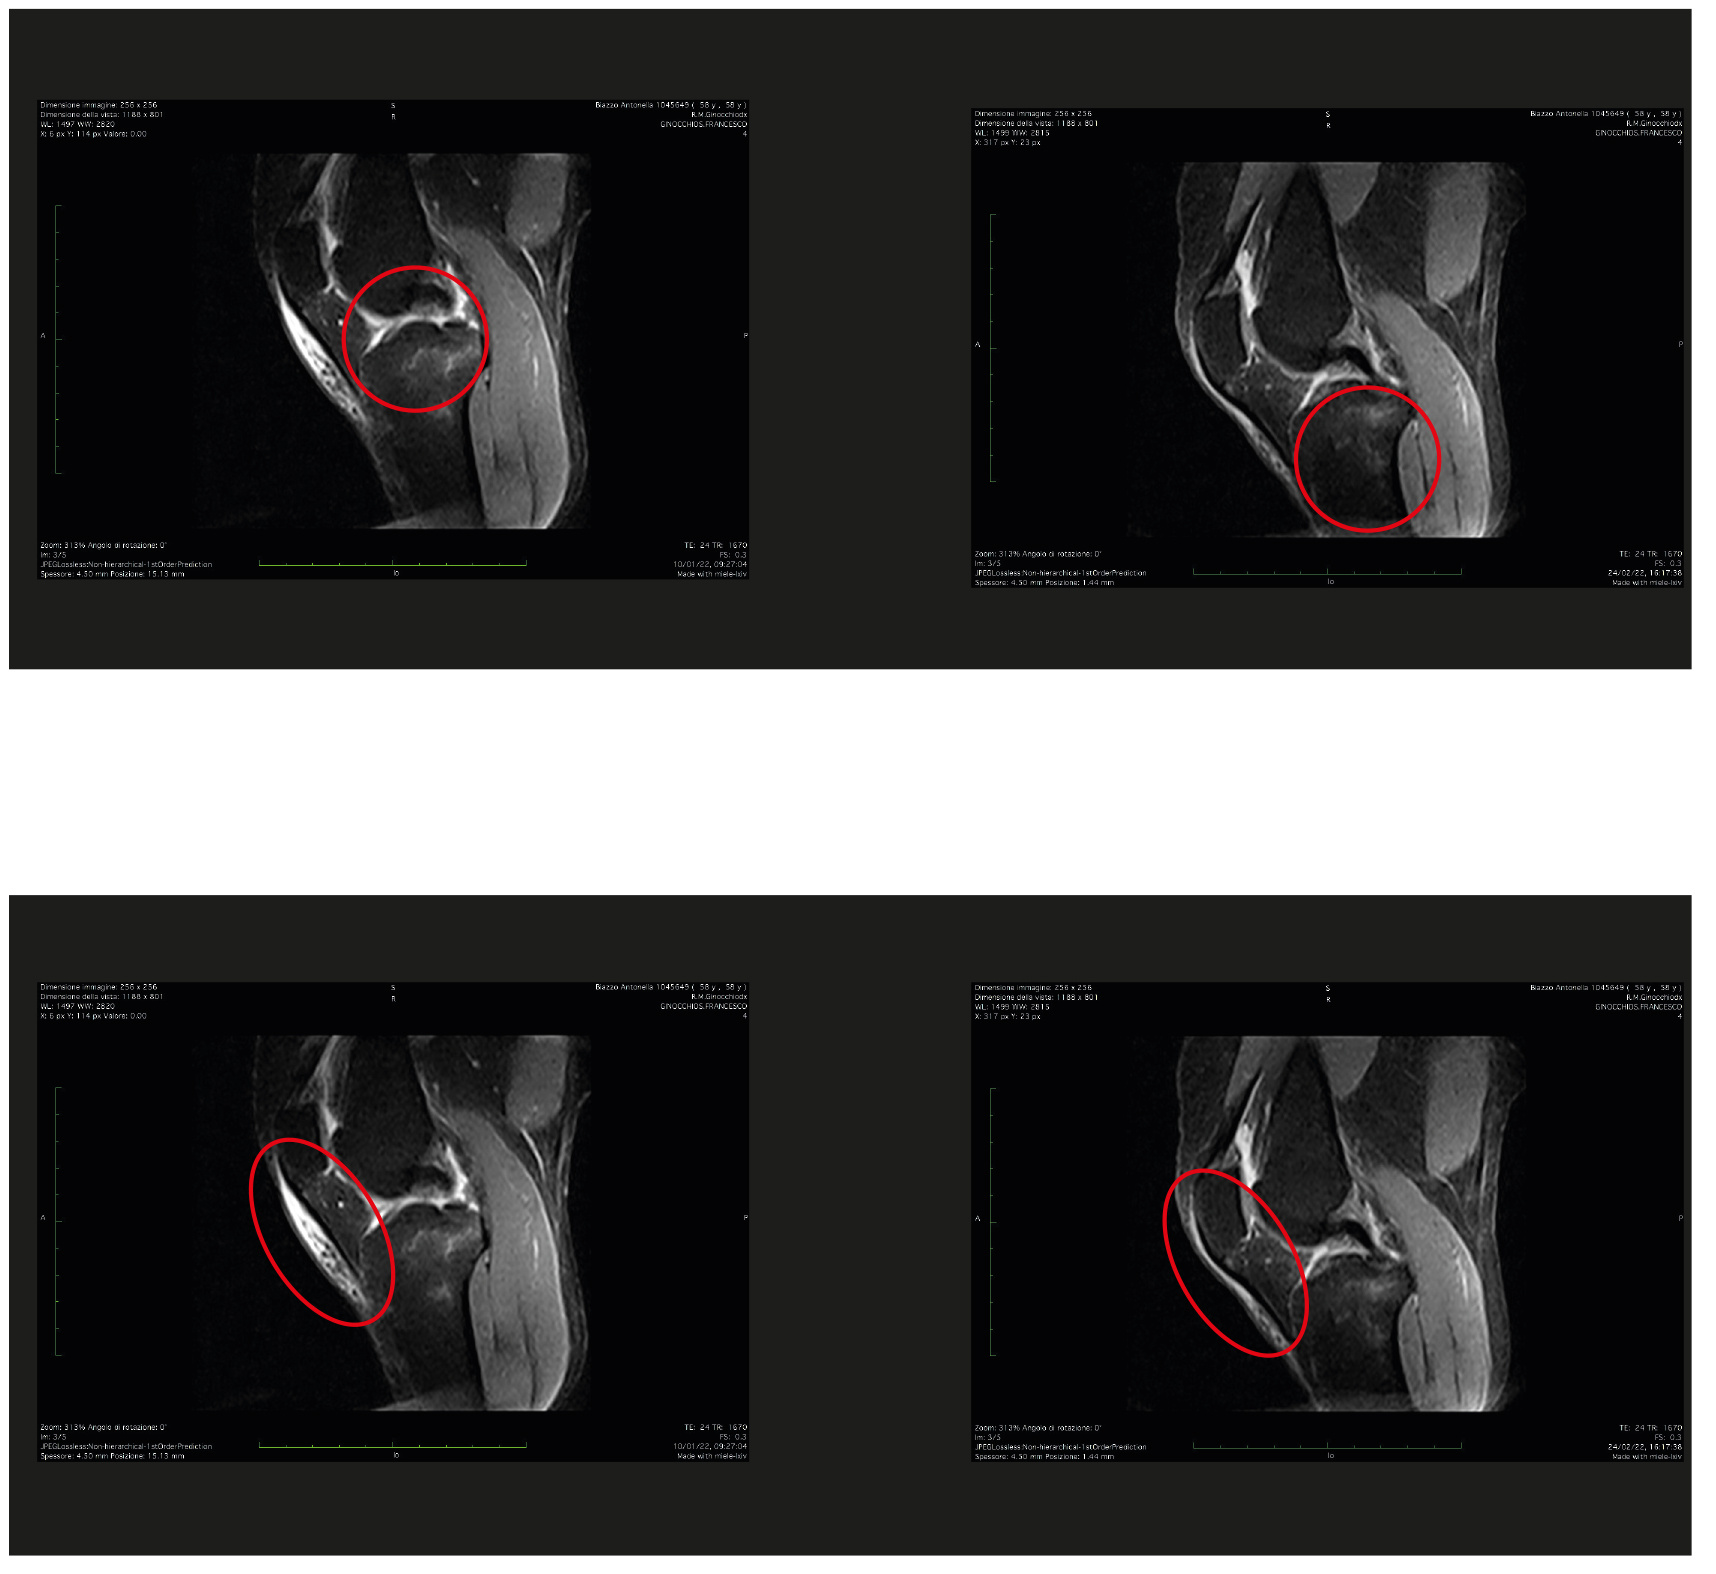

Caso Clinico (RM) e Studi Clinici

Eur J Musculoskel Dis 2024 Sep-Dec;13(3):40-46 - Ossigeno ozono terapia transdermica, innovazione terapeutica conservativa della retrazione fascia tricipitale e avampiede.

Studio osservazionale nel runner.